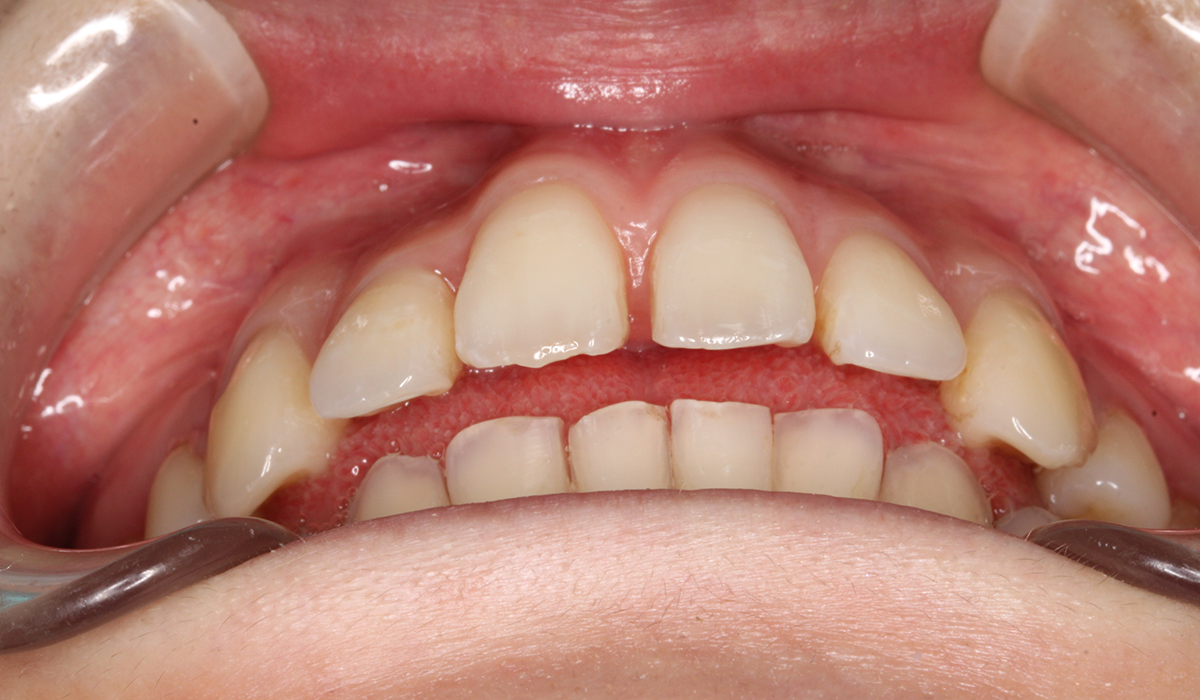

正面

術前